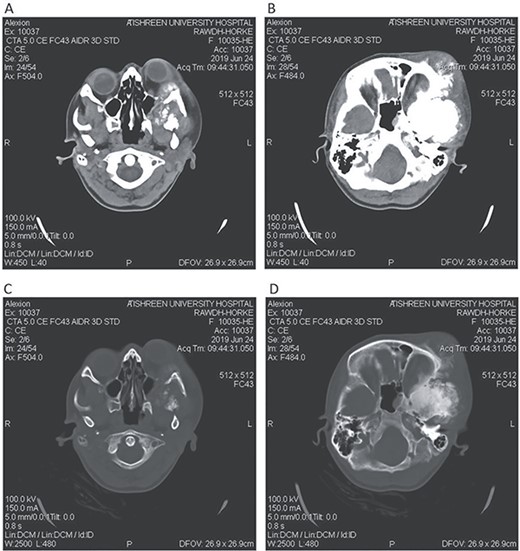

CT head tissue window. A, B. Invasion and destruction of the surrounding tissue. C. Minor shift of the elements of the midline to the right side due to the edema. D. The edema applies pressure to the left lateral ventricle.

A 17-year-old female presented with a history of osteosarcoma that was confirmed after undergoing a surgery to remove an enlarging bone tumor in the left temporal region 2 years ago. She later got pregnant and delivered her child but never got back for a checkup until she was admitted to our hospital with a severe and unresponsive to medication headache that progressed over the course of 6 months and blurred vision that progressed to complete left-sided vision loss. Physical examination revealed a tough and mobile yet fixed at the base 7-cm mass towards the left of the frontal bone. Many more masses were revealed in the left side of the skull including the anterior cranial fossa, orbit, base of the skull and the left part of the occipital region where the previous procedure was performed (Fig. 1). These masses had been increasing in size probably under the influence of pregnancy hormones causing pain that radiated along the orbital and maxillary branches of the left trigeminal nerve. Physical examination and past medical history were otherwise unremarkable. Laboratory tests were all normal, and her family history was negative. Staging studies showed no evidence of distant metastatic disease in the chest, the abdomen and the pelvis. CT scan of the skull revealed a bone-forming non-lytic lesion accompanied by periosteal reaction. This lesion bulges to the outside towards the scalp spreading into both the soft tissues and the inside of the entire left side of the skull with a sunburst-pattern (Figs 2 and 3). Its rims are unsymmetrical and pointy, and it bulges into the left orbit outside the muscles causing exophthalmos with a semi-complete proptosis of the eyeball out of the orbit (Figs 2 and 3). This lesion applies pressure to the left frontal and temporal lobes causing mild edema in both these lobes without invading the brain tissue. This edema in turn applies pressure to the left lateral ventricles (minor shift of the elements of the midline to the right side can be seen on CT) (Fig. 4). Due to the tumor’s wide spread, the surgical procedure was performed in two stages (approximately 6-hour-long each). In the first stage, the bone mass was removed through a procedure of wide skull approach including the frontal, temporal and parietal bones and a removal of the invading part of the temporal muscle. Moreover, the lateral wall and roof of the left orbit were removed, the left optic nerve was dissected free and part of the meninges was removed and replaced with an autogenic patch from the fascia lata. Then, the bone loss was compensated for by using bone cement Synicem VTP (poly methyl methacrylate and Barium sulfate), and the orbit was rebuilt; the eyeball was placed back with noticeable decline of the exophthalmos. In the second stage, a complementary left parietal occipital incision of the previous approach was performed 3 weeks later; the remaining of the frontal and occipital bones was removed, and a partial mastoid surgery was done. Furthermore, the cavernous sinus were revealed and found to be not invaded. Later on, the normal skull shape was restored using the same cement. The histopathology of the lesion revealed proliferation of neoplastic chondroblasts, osteoblasts and spindle-shaped cells. The features are consistent with low-grade chondroblastic osteosarcoma (Fig. 5). The patient did not need ICU admission. She recovered well 3 days after the surgery and was discharged with no deficits. A CT scan that was performed post-operatively revealed that the masses were successfully excised (Figs 6 and 7). At the last follow-up 1 month post-operation, the patient was scheduled to undergo a course of radiotherapy, 60 Gy of radiotherapy in 30 fractions over 4 weeks without chemotherapy, as it is not recommended with low-grade osteosarcoma.